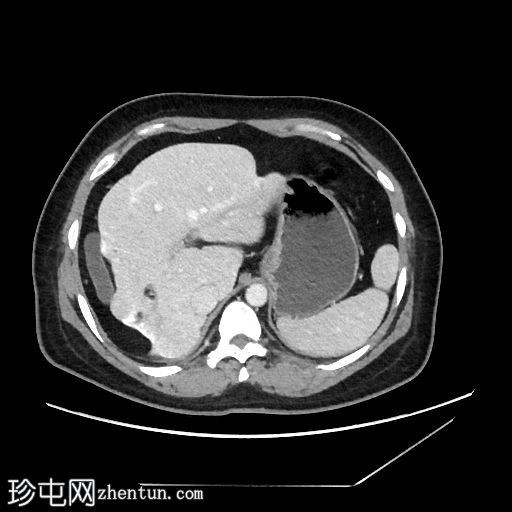

轴位增强扫描(门静脉期)